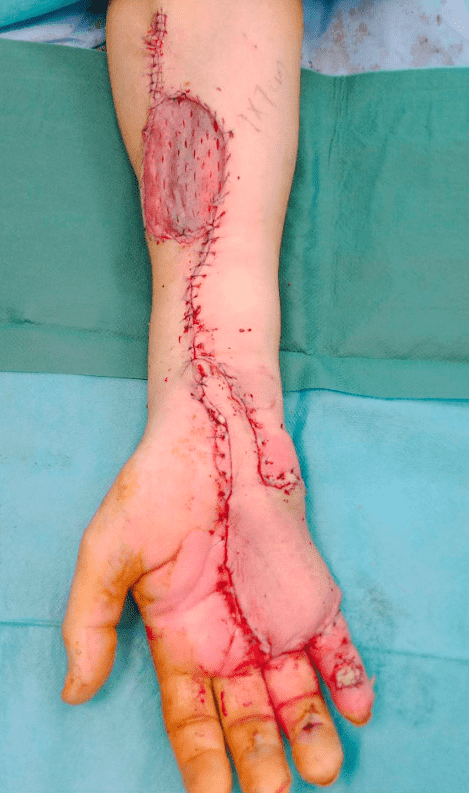

Side view after flap inset

The flap is inset into the defect using meticulous suturing techniques, ensuring tension-free closure. If venous congestion is noted, adjustments may be made, including optimizing cephalic vein outflow or using a microvascular anastomosis if required.

Functional flap and complete healing of the donor site with a STSG. Only a minor defect of about 10×15 mm on the fifth digit distally remained, which was planned to heal conservatively.